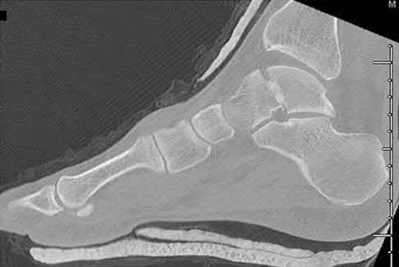

Figure 28 is the lateral radiograph of a patient who sustained an intra-articular fracture of the calcaneus. The structure (*) depicted by the arrows most likely represents which osseous component of the calcaneus?

Fractures of the calcaneus occur as a result of shear and compression forces. Foot position at the time of impact, the force of the impact, and bone quality all dictate the degree of comminution and fracture line orientation. Two primary fracture lines are consistently observed, one of which divides the calcaneus into medial and lateral portions. An essential feature of this fracture

line is that it creates a fragment (sustentaculum tali) that remains attached to the talus by the interosseous ligament. This medial portion (constant fragment) of the posterior facet retains its normal anatomic position beneath the posterior talus. Its corresponding lateral component (labeled with an * in the figure), however, can be found displaced inferiorly within the body of the calcaneus. It is often rotated 90 degrees (as depicted in Figure 28) in relation to the remainder of the subtalar joint. This gives the appearance of what has been described as the "double-density" sign. The middle facet is more anterior and less commonly displaced. The lateral wall is nonarticular.